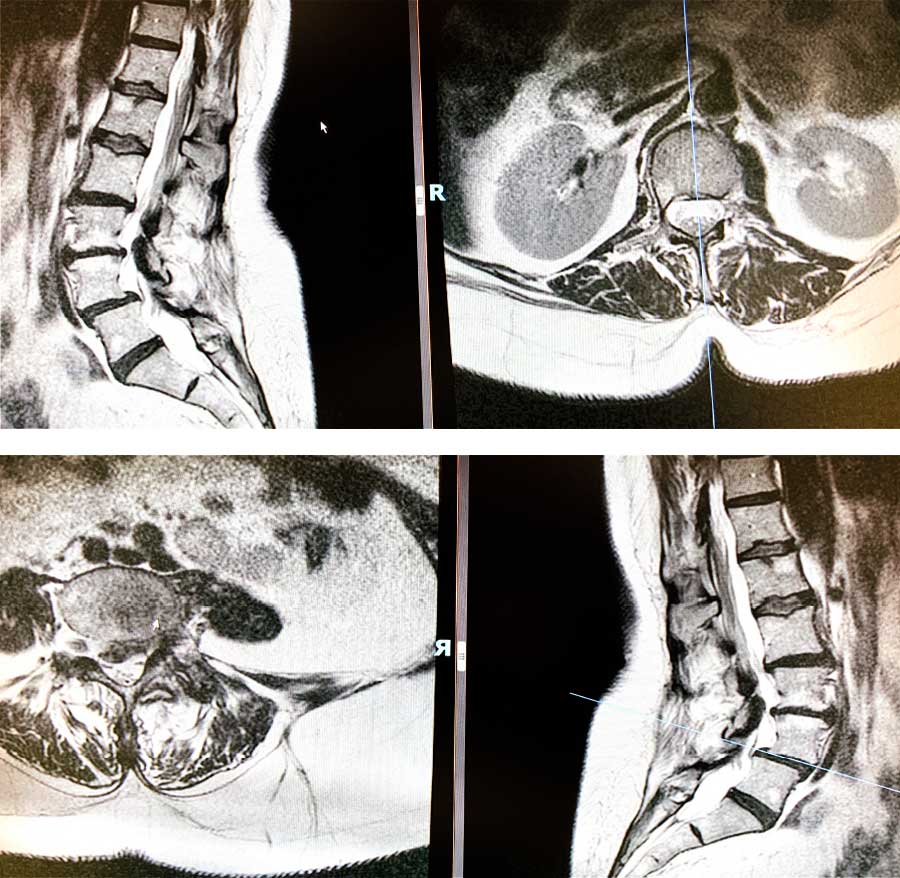

Tras conocer esta información, ya pudimos conocer el territorio donde teníamos que ir para buscar la patología. Tal y como hemos hecho en casos clínicos similares, le realizamos una resonancia y objetivamos que la raíz L5S1 tenía un quiste sinovial que comprimía dicha raíz.

Además, en las raíces L4 y L5 tenían una leve listesis. Esto significa que la vértebra cuarta, con respecto a la vértebra quinta está un poco desplazada y provoca en la paciente una pequeña hernia que le comprime la raíz L4 y probablemente también afecte a la L5.